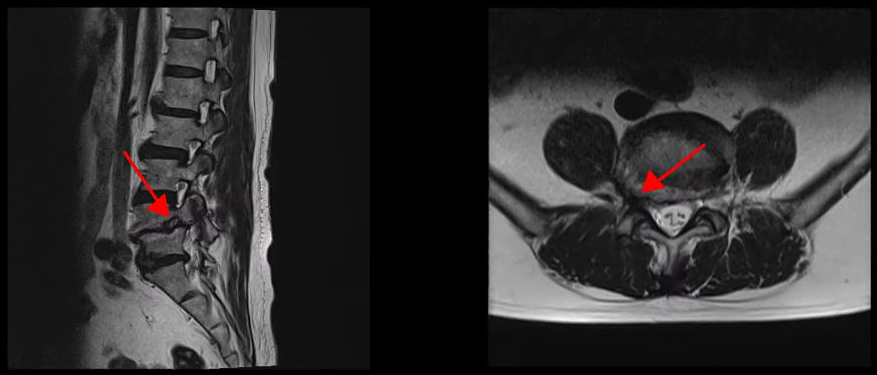

<4-5번 추간공협착증>

<4-5번 척추전방전위증>

이 환자분은 요추 4-5번 오른쪽에 심한 추간공협착증, 2단계의 전방전위증이 있으며, 특히 전방전위증으로 인해 추간공이 매우 좁아져 있습니다. 또 요추 5-1번 왼쪽에 디스크 파열이 있습니다.